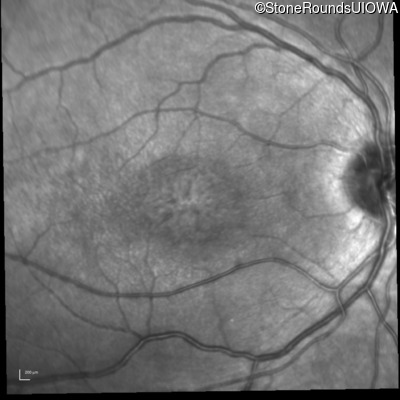

Infrared Fundus Photograph - Right - 20/63 -2

Exemplar

Infrared Fundus Photograph - Left - 20/50 -2